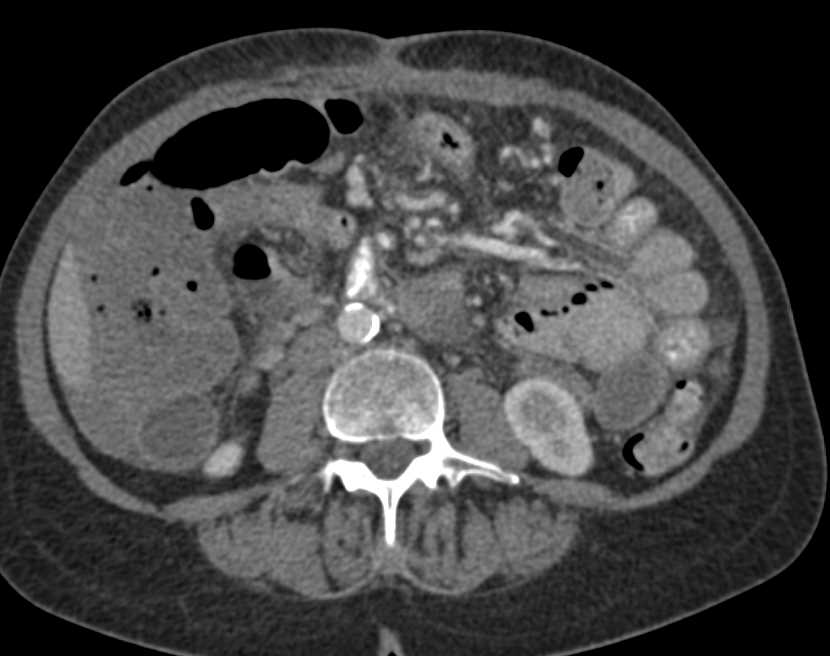

Metastatic Melanoma to the Small Bowel